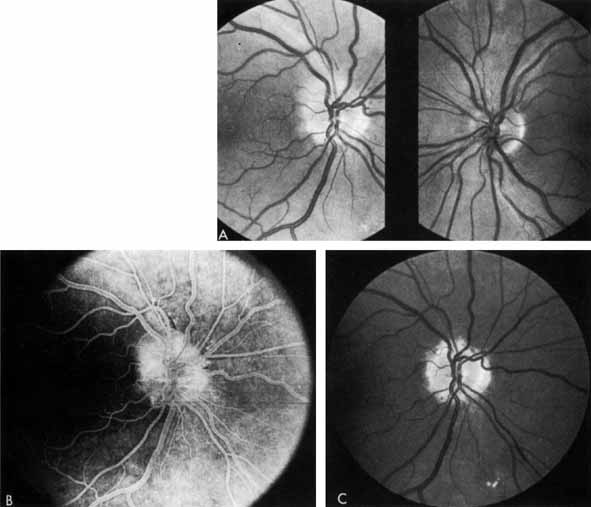

To prevent new areas of neovascularization, several ophthalmologists began to photocoagulate not only neovascularization but all intraretinal hemorrhages as well (“shoot the red”), on the grounds that they represented areas of hypoxia that could later develop into proliferative retinopathy. They soon noted that the cases that had the most intraretinal hemorrhages and therefore received the most initial photocoagulation frequently had the best long-term results, with permanent regression of neovascularization (Fig. 20). In such cases, the optic disc often became pale, indicating optic atrophy.

Fig. 20 A. Neovascularization of the disc (NVD) and a small vitreous hemorrhage. Panretinal photocoagulation was given. B. Two months later, the NVD has completely regressed.

At about the same time, Aiello and co-workers,132,133 and others134–137 noted that patients with unilateral high myopia, extensive chorioretinal scarring, glaucoma, and optic nerve atrophy frequently had markedly asymmetrical retinopathy. The prior retinal or optic nerve damage seemed to protect that eye from diabetic retinopathy (Fig. 21). These investigators initiated the concept of PRP (Fig. 22). They theorized that photocoagulation burns scattered throughout the retina would decrease the retina's need for oxygen and thereby prevent neovascularization from developing or might even cause regression of existent neovascularization. Early studies showing the benefits of PRP were criticized on statistical and other grounds and were not widely accepted.138,139

Fig. 21 A. Right eye of a patient with neovascularization of the disc (NVD), numerous retinal hemorrhages, soft and hard exudates. B. Left eye of the same patient. Note pale optic disc from previous ischemic optic neuropathy and minimal diabetic retinopathy.